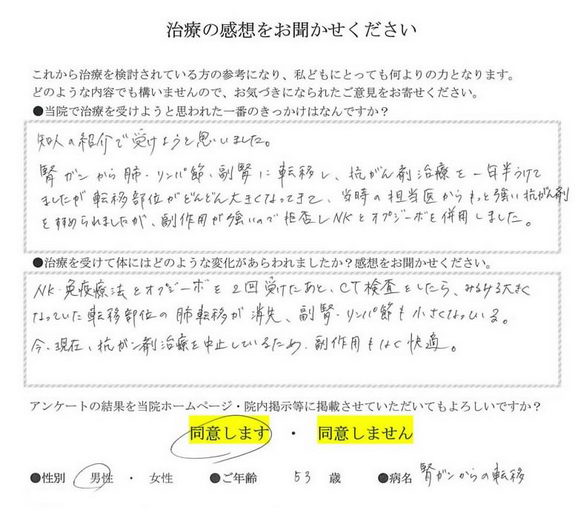

油门+刹车疗法®接受治疗患者的心声

胃癌转移(53岁 男性)癌症免疫疗法+抗PD-1抗癌剂2疗程

通过朋友的介绍开始了治疗。 肺.淋巴结.肾上腺.有转移.当时进行了1年半的抗癌剂治疗.但是转移部位的肿瘤越来越大.当时的主治医生建议.使用更强的抗癌剂.但是因为有着强烈的副作用所以没有进行.进行的是NK和抗PD-1抗癌剂疗法.2回的治疗.之后CT检查中越来越大的 肺部肿瘤消失.肾上腺.淋巴结也变小了.目前.以中断抗癌剂治疗.没有任何副作用.稳定的状态.